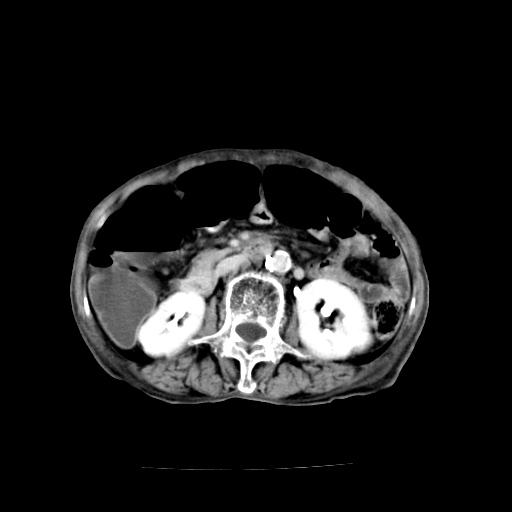

女,68岁,腹胀、恶心两周,先做ct平扫,当时家属不同意强化,6天后家属要求增强扫描。

1)不排除胃窦癌;建议行胃镜检查。 2)局灶性脂肪肝。腹水。

支持考虑1、胃窦癌?建议行胃镜!; 2、局灶性脂肪肝。  3、双侧胸腔积液,胸膜增厚

不均匀脂肪肝,胃腔改变须结合钡餐或胃镜观察